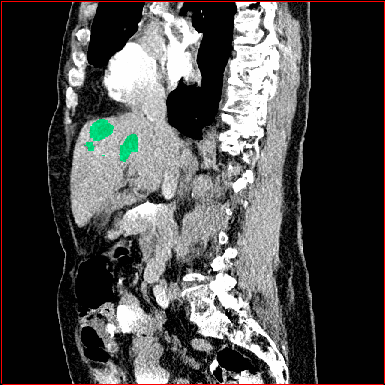

Figure 3 shows the generalizability of MAISI-v2 ControlNet for different body regions and voxel sizes. Figure 4 shows qualitative results for MAISI-v2 ControlNet on 5 types of tumors.

Figure 3: MAISI-v2 segmentation-guided results for small to large volume size and three different regions.

Lung Tumor

0.75×0.75×0.60.75\times 0.75\times 0.6

mm

512×512×512512\times 512\times 512

Figure 4: MAISI-v2 segmentation-guided results for five types of tumors. We show results for different voxel spacing and volume size to demonstrate the flexibility of MAISI-v2. Different Hounsfield Unit window is used to better show the contrast between tumor and normal tissues.